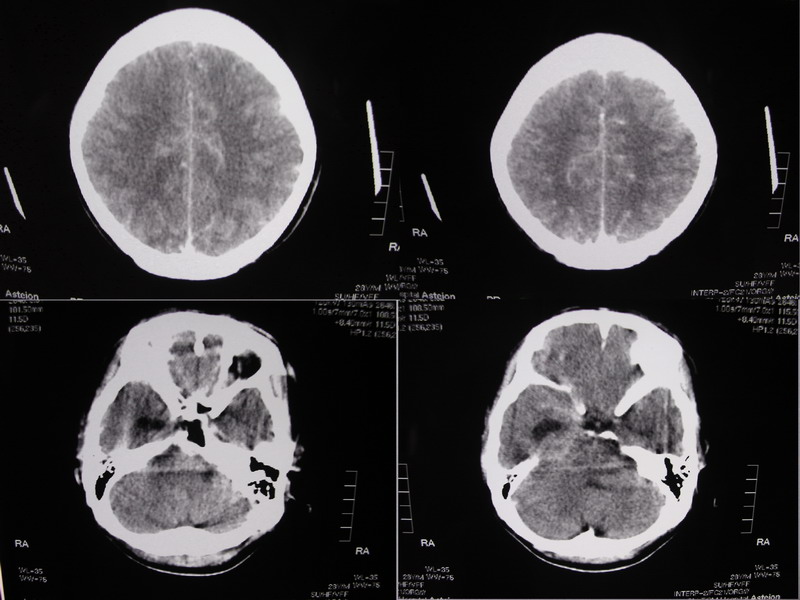

以下是引用余辉在2007-5-14 17:03:00的发言:[br]右侧脑室颞极后方可见高密度块状影,颞极呈杯口状推挤前移,右侧大脑脚及丘脑上部受推挤向对侧移位,右丘脑区结构紊乱,增强扫描病灶有不规则强化,以下部颞极后方为著。胼胝体压部及右枕叶视辐射区低密度改变,右基底节区低密度改变,双侧脑室不对称积水征象,意见:1颞极后方—右丘脑区占位性病变,如室管膜瘤等2脑血管疾病如moyamoya,局部脑血管畸形等3脑膜炎等后遗改变,建议mr及脑血管造影检查[br][br][本贴已被 余辉 于 2007-5-14 17:05:26 修改过]

以下是引用千里草在2007-5-14 15:54:00的发言:[br]考虑:1、双侧梗阻性脑积水;[br] 2、右侧基底节区缺血性脑血管疾病。

以下是引用qiuleiyu在2007-5-14 18:43:00的发言:[br]支持;1,交通性脑积水(病脑后遗征?)2,右基底节及胼骶体压部低密度灶伴轻度占位表现,结合年龄考虑moyamoya,建议dsa.[br]